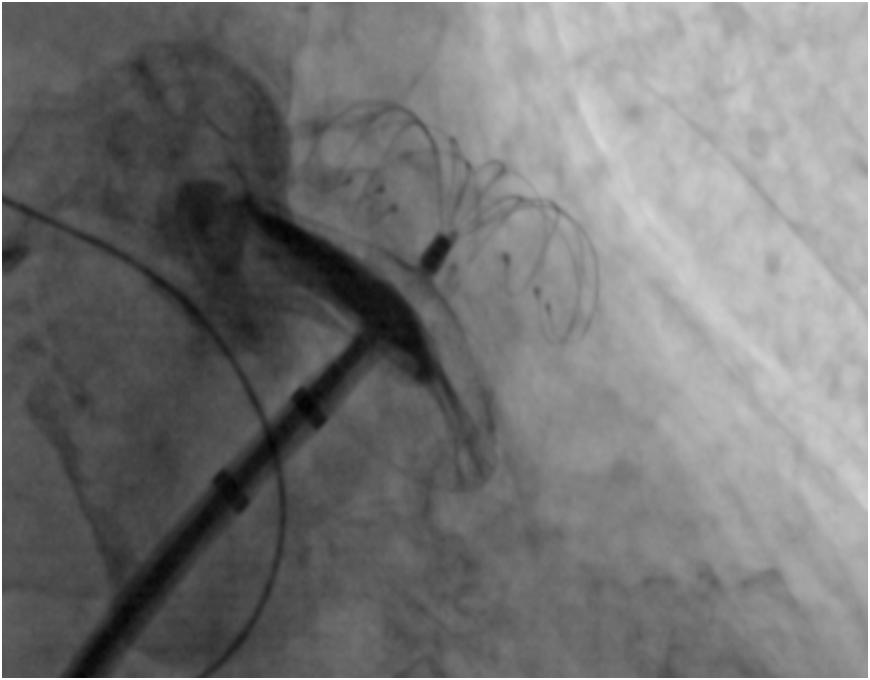

经过前期的充足准备,在仁济医院心内科主任卜军教授、西院徐瑾教授和宝山分院黄剑锋教授团队共同合作下手术成功实施。在心腔内超声(ICE)和CARTO3三维标测系统指引下,团队无缝衔接,完美配合顺利开展了左心耳封堵和房颤导管消融手术。术后,在医务人员的精心治疗及护理下,目前患者身体健康良好。

什么是左心耳封堵手术?经皮左心耳封堵手术是一项房颤卒中预防的国际先进技术,主要针对合并心房颤动又不宜长期服用抗凝药物的患者,微创治疗,无需开胸,整个手术可在1小时左右完成,成功进行左心耳封堵术可实现“一次植入,终身预防”,从而提高房颤患者生活质量。

房颤射频消融术即通过微创介入技术,采取射频能量局部加热的方式,逐点消融来隔离肺静脉对电信号的传导,从而防止房颤发作。